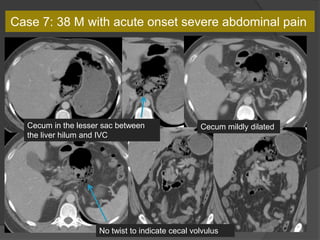

Case 7: 38 M with acute onset severe abdominal pain

Cecum in the lesser sac

Cecum mildly dilatedCecum in the lesser sac between

the liver hilum and IVC

No twist to indicate cecal volvulus

Dx: Lesser sac hernia with cecal incarceration

Take home points-

1. Look for abnormal location of a bowel loop indicating an internal

hernia

2. Abnormal dilatation of the abnormally located loop may indicate

incarceration

3. Absence of beak sign or mesenteric twist can exclude volvulus

Lesser sac hernia via the foramen of

Winslow

Review of Internal Hernias: Radiographic and Clinical Findings. LC Martin et

al. AJR March 2006

Lesser sac hernias comprise 8% of all

internal hernias which have a less than 1%

overall incidence.

Circumscribed loop posterior and medial to

the stomach

Case 7: 38M with acute onset severe abdominal pain

• 147.

Cecum in thelesser sac Cecum mildly dilatedCecum in the lesser sac between the liver hilum and IVC No twist to indicate cecal volvulus Case 7: 38 M with acute onset severe abdominal pain

• 148.

Dx: Lesser sachernia with cecal incarceration Take home points- 1. Look for abnormal location of a bowel loop indicating an internal hernia 2. Abnormal dilatation of the abnormally located loop may indicate incarceration 3. Absence of beak sign or mesenteric twist can exclude volvulus

• 149.

Lesser sac herniavia the foramen of Winslow Review of Internal Hernias: Radiographic and Clinical Findings. LC Martin et al. AJR March 2006 Lesser sac hernias comprise 8% of all internal hernias which have a less than 1% overall incidence. Circumscribed loop posterior and medial to the stomach